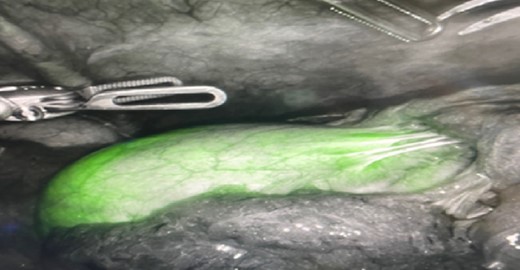

In the peri-operative period, a bolus ICG solution (2.5 mg in 10 mL of sterile saline) was administered intracystically via percutaneous cholecystostomy drain within 1 hour of the operative start time. An infra-umbilical incision was made, and a Hasson trocar was placed and insufflated with 15 mmHg of carbon dioxide. A laparoscope was inserted to inspect the abdomen. An 8 mm 30-degree laparoscope was introduced, and three additional 8 mm trocars were placed, one in the epigastrium and two in the right upper quadrants. Laparoscopic near-infrared cholangiograms were captured using the Firefly system on the DaVinci robot, as demonstrated in Figs 2 and 3A and B and 4A) with Fig. 4B displaying the gallbladder fossa after removal.

PCDC tract after administration of ICG. (A) is prior to surgical removal of gallbladder, (B) is postoperative liver bed.